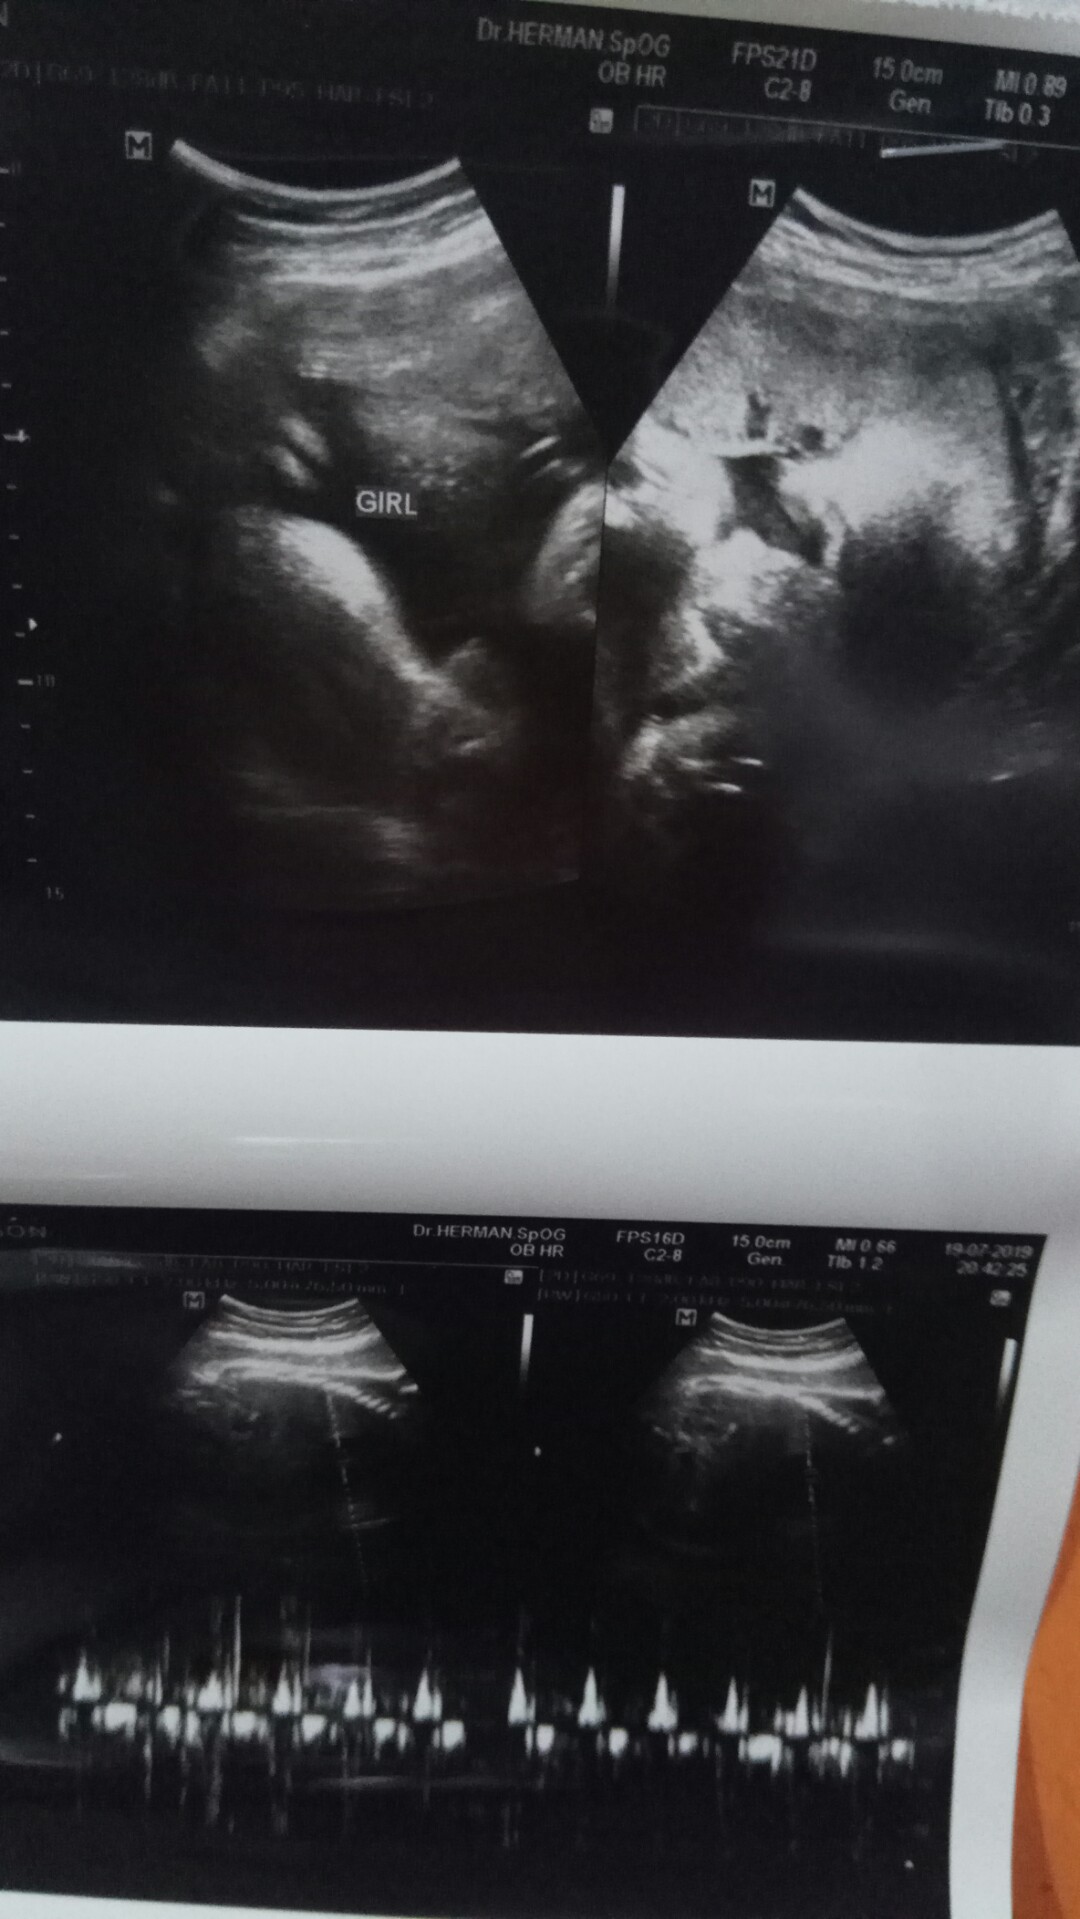

25 september .insyaAllah cewek bun

Hpl 9/9/2019... Baby girl 😍